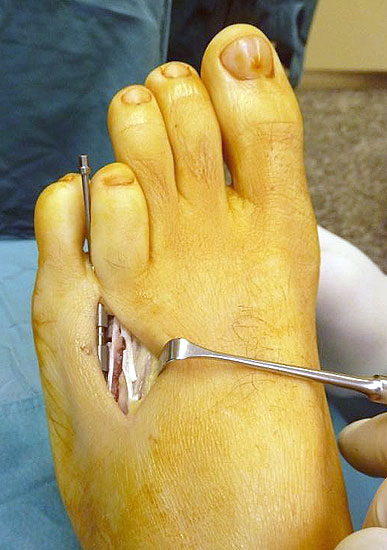

Das im Folgenden vorgestellte Operationsverfahren beschreibt die Kallusdistraktion von Metatarsalia nach den Prinzipien von Ilisarov 21 unter Verwendung eines internen, winkelstabilen Titan-Minifixateur (Klauser 2009). Der interne Distraktor ermöglicht während der Distraktions- und der Durchbauungsphase aufgrund seiner hohen Stabilität je nach Modell (18 mm, 23 mm) eine Verlängerung von bis zu 25 mm. Nach interner Anlage des Minifixateurs, meist lateral, kann über eine kontinuierliche Kallusdistraktion der Metatarsalebogen unter frühzeitiger Mobilisation im Gips oder Short-Walker rekonstruiert werden 15. Über einen interdigital und transcutan ausgeleiteten Aktivatorstab wird die Distraktion vom Patienten selber täglich morgens und abends durchgeführt. Zusätzlich vorliegende Strahlpathologien, wie zum Beispiel eine verkürzte Strecksehne oder ein kontraktes Metatarsophalangealgelenk können im Rahmen der Erstoperation ebenso therapiert werden wie z.B. ein Hallux valgus, ein Hallux valgus interphalangeus und/oder ein Digitus quintus varus (Klauser 2009). Nach Rekonstruktion des Metatarsalebogens wird in einem zweiten, kleinen Eingriff der Aktivatorstab über eine Spezialpinzette diskonnektiert und entfernt, wobei der Distraktor als interne Fixation belassen wird. Die Entfernung des Distraktors erfolgt in der Regel nach 9 – 12 Monaten, da es sich meist um angeborene kindliche Fehlbildungen handelt (Brachymetatarsie) und eine operative Intervention frühzeitig im Kindesalter erfolgen sollte (Klauser 2009).

• Percutane Ausleitung des Aktivatorstabes, über den die Kallusdistraktion vorgenommen wird, was eine frühzeitige Mobilisation im Gips oder Short Walker ermöglicht (Klauser 2009).

• Laterale Implantation des Distraktors und damit besseres Anmodellieren entsprechend der ovalen Knochenstruktur des Os metatarsale und somit - sowie aufgrund der geringen Aufbauhöhe des Minifixateur - gute Weichteildeckung (Klauser 2009).

• Zweiter Eingriff: Diskonnektieren des transcutan ausgeleiteten Aktivator, falls möglich, über eine kleine Inzision von 1,5 bis 2 cm, in der Regel jedoch über Eröffnen der alten Schnittführung mit ggf. Strecksehnenverlängerung und erneutem Grundgelenk-Release sowie ggf. Ausleiten einer Penroselasche oder einer Gentamycin-Palacos-Minikette.